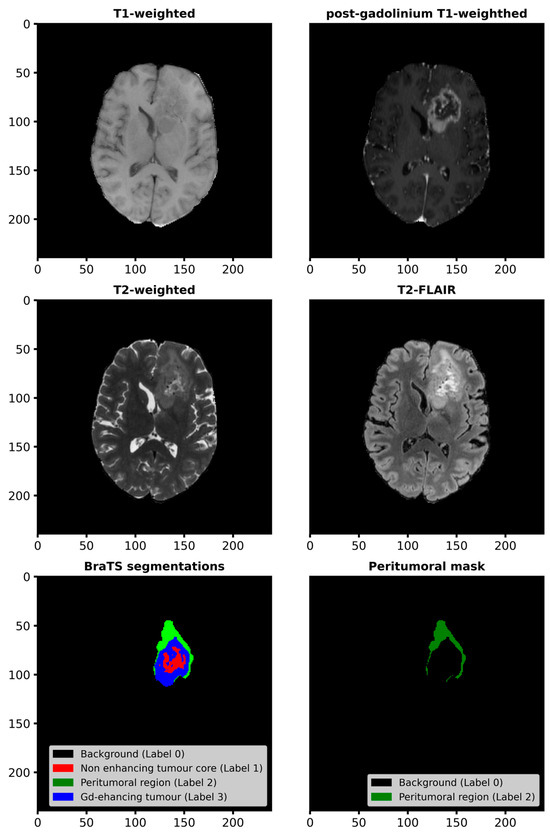

2.2. Methods

2.2.1. Workflow for Radiomic Feature Extraction and Tumor Classification

2.2.2. Radiomic Feature Extraction